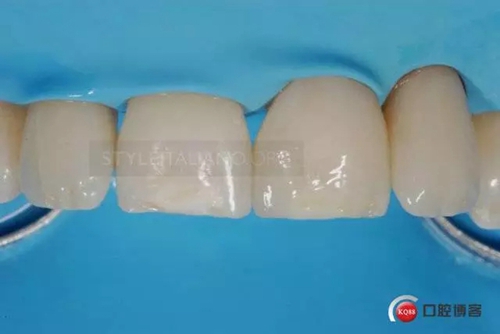

4 years check

336370.jpg

10 years check